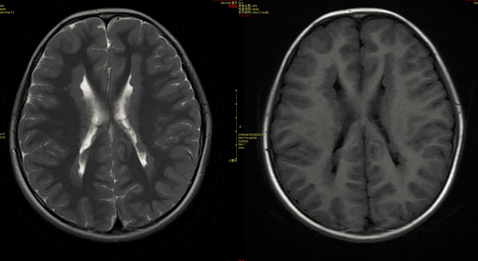

脑灰质异位,脑灰质异位图片

脑灰质异位_人体磁共振成像解

典型病例-脑灰质异位症

脑灰质异位症1例

脑灰质异位

医影学堂丨八个病例带你看懂脑灰质异位的三种类型